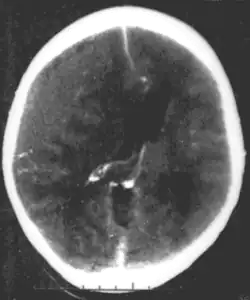

Diagnóza je stanovena pomocí CT; hematom je vidět při vyšetření jako bikonvexní hyperdenzní útvar u kostí lebky, často u místa zlomeniny. Léčbou je neurochirurgické odstranění hematomu a podvaz krvácející arterie, venózní krvácení lze léčit konzervativně za monitorace CT.[2]